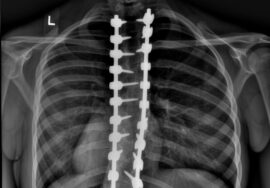

يُعد اعوجاج العمود الفقري (الجنف) من المشكلات المنتشرة بين الأطفال والمراهقين، وقد يسبب القلق للأهل بسبب تأثيره على شكل الظهر وصحة الجسم العامة. ومع تطور الطب الحديث، أصبح حزام اعوجاج العمود الفقري أحد الحلول غير الجراحية الفعالة لتقويم العمود الفقري والحد من تفاقم الانحناء.

عندما تكون زاوية الانحناء بين 20 و45 درجة.

يقوم الطبيب بمراجعة الحالة كل فترة عن طريق الأشعة السينية لمتابعة مدى تحسن زاوية العمود الفقري وتعديل خطة العلاج إذا لزم الأمر.